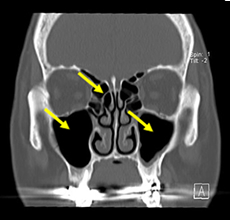

慢性副鼻腔炎(ちくのう症)

ヒトの鼻はいくつもの空洞に分かれており、それらを副鼻腔といいます(図4)。それぞれの副鼻腔は自然口という小さな通路でつながっていますが、この通路が炎症などでふさがると副鼻腔内で炎症を起こし、粘膜が腫れて粘液がたまります。この状態が長引いたものが慢性副鼻腔炎で、膿がたまると蓄膿症という状態になります。たまった粘液がさらに粘膜の炎症を引き起こし、鼻茸(ポリープ)を増生させることがあります(図5)。ポリープによってにおいの分子が嗅神経に届かないと、嗅覚障害をもたらすことがあります。嗅覚が低下すると味も感じにくくなる味覚障害を自覚することもあります。慢性副鼻腔炎を治すことで、嗅覚障害が改善します。

体が成長する発育過程において様々な原因で鼻中隔が湾曲して息の通りが悪くなります。外見からはわかりませんが、CTで確認すると(図8)、鼻中隔が大きく曲がっていることが分かります(黄色矢印)。湾曲の程度が軽度の場合には問題ありませんが、重度の場合には片方の鼻閉を常に自覚し、空気の通過障害を起こして粘膜の障害を生じやすくなるといわれています。